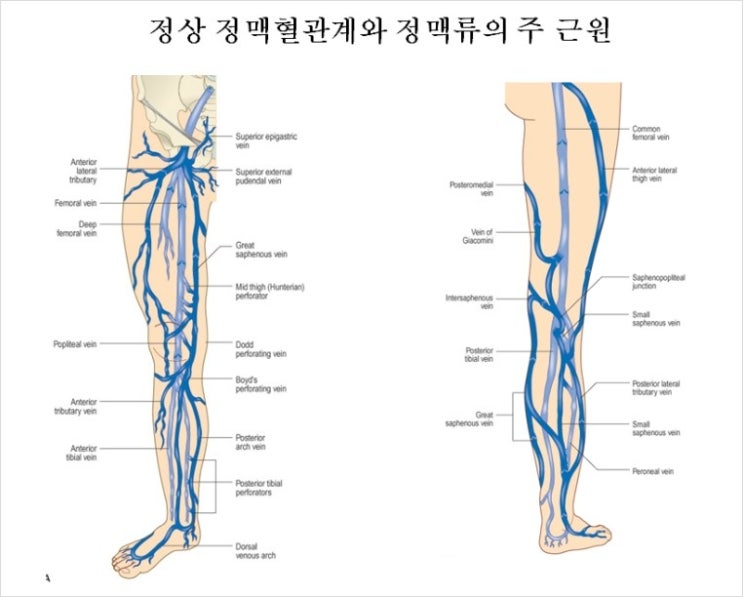

하지 정맥 검사는 하지 정맥의 기능과 구조를 평가하는 진단 검사입니다. 이 검사는 보통 정맥을 시각화하고 혈류를 평가하기 위해 초음파 기술을 사용하여 이루어집니다. 이 검사 결과는 심부정맥혈전증(DVT)과 정맥류 등의 상태를 진단하고 치료 옵션을 안내하는 데 도움이 됩니다. 족실정맥검사 : 자세히 보기

정맥류 검사는 하지 정맥류의 기능이나 구조를 평가하는 비 침습적 진단 검사입니다. 다리 정맥. 시험 도중 환자는 검사 테이블에 눕고 기술자는 다리의 피부에 젤을 바릅니다. 그 후, 변환기라는 휴대용 장치를 피부 위에 이동해 정맥과 주변 조직에서 반사하는 고주파 음파를 방출합니다. 이 음파는 모니터에서 볼 수 있는 화상에 변환됩니다. Leg Chamber Vein Exam은 정맥의 혈류를 평가하고 정맥 구조의 이상을 감지할 수 있습니다. 다리 깊은 정맥에 형성되는 혈전인 마음 부정맥 혈전증(DVT) 같은 상태를 진단하는데 도움이 됩니다. DVT는 바로 치료하지 않으면 목숨을 위협하는 상태에 빠질 가능성이 있습니다. 발에 바 정맥 검사는 다리에 통증, 부종, 불쾌감을 유발할 수 있는 풍만함, 왜곡된 정맥인 정맥류도 감지합니다. 발에 바 정맥 검사는 혈관 질환의 치료 선택 사항을 안내할 수 있는 유용한 진단 툴입니다. 상황. 예를 들어, 환자가 DVT진단을 받은 경우, 발에 바 정맥 검사는 혈전의 위치와 범위를 결정하는데 도움이 됩니다. DVT의 치료 옵션에는 혈액 희석제 또는 혈전 용해제가 포함되는 경우가 있고 다리에 바 정맥 검사 결과는 어느 치료 옵션이 가장 적합한지를 결정하는데 도움이 됩니다. 정맥 검사는 최상의 진료 프로세스를 결정하는데 도움이 됩니다.

정맥류 치료 옵션에는, 생활 습관의 변화, 압박 스타킹, 또는 경화 요법이나 정맥 레이저 치료 등 최소 침습 절차가 포함되는 경우가 있습니다. 하지심 정맥 검사 결과는 환자에게 최적의 치료 방법을 결정하는데 도움이 됩니다. 정맥류 검사는 안전하고 비 침습적인 진단 검사로 정맥의 기능이나 구조에 관한 유용한 정보를 제공합니다. 다리 정맥. 검사는 통상, 진료소와 병원 환경에서 열리고 특별한 준비는 필요 없습니다. 환자는 발에 접근이 쉬운 넉넉한 옷을 입어야 하고 검사 전에 피부에 로션이나 오일을 바르는 습관은 피해야 합니다. 결론으로서 발에 바 정맥 검사는 다음과 같은 중요한 진단 툴입니다. 심정맥 혈전증이나 정맥류 등의 혈관 상태 진단 및 치료 선택 사항을 안내합니다. 이 검사는 안전하고 비 침습적인 다리 정맥의 기능과 구조에 관한 귀중한 정보를 제공합니다. 발에 통증, 부종, 또는 불쾌감과 같은 증상이 나타나면 다리의 챔버 정맥 검사가 당신에게 적합한지를 담당 의사와 상담하세요.

정맥류 치료 옵션에는 생활 습관의 변화, 압박 스타킹 또는 경화 요법이나 정맥 내 레이저 치료 등의 최소 침습 절차가 포함될 수 있습니다. 하지심 정맥 검사 결과는 환자에게 최적의 치료 방법을 결정하는 데 도움이 됩니다. 정맥류 검사는 안전하고 비침습적인 진단검사로 정맥의 기능과 구조에 대한 유용한 정보를 제공할 수 있습니다. 다리 정맥. 검사는 일반적으로 진료소나 병원 환경에서 이루어지며 특별한 준비가 필요하지 않습니다. 환자는 발에 쉽게 접근할 수 있는 넉넉한 옷을 입어야 하며 검사 전 피부에 로션이나 오일을 바르는 것은 피해야 합니다. 결론적으로 족챔버 정맥검사는 다음과 같은 중요한 진단 도구입니다. 심부 정맥 혈전증이나 정맥류 등 혈관 상태 진단 및 치료 옵션을 안내해 드립니다. 이 검사는 안전하고 비침습적이며 다리 정맥의 기능과 구조에 대한 귀중한 정보를 제공할 수 있습니다. 다리에 통증, 붓기 또는 불쾌감과 같은 증상이 나타나면 다리 챔버 정맥 검사가 당신에게 적합한지 여부를 담당 의사와 상담하십시오.